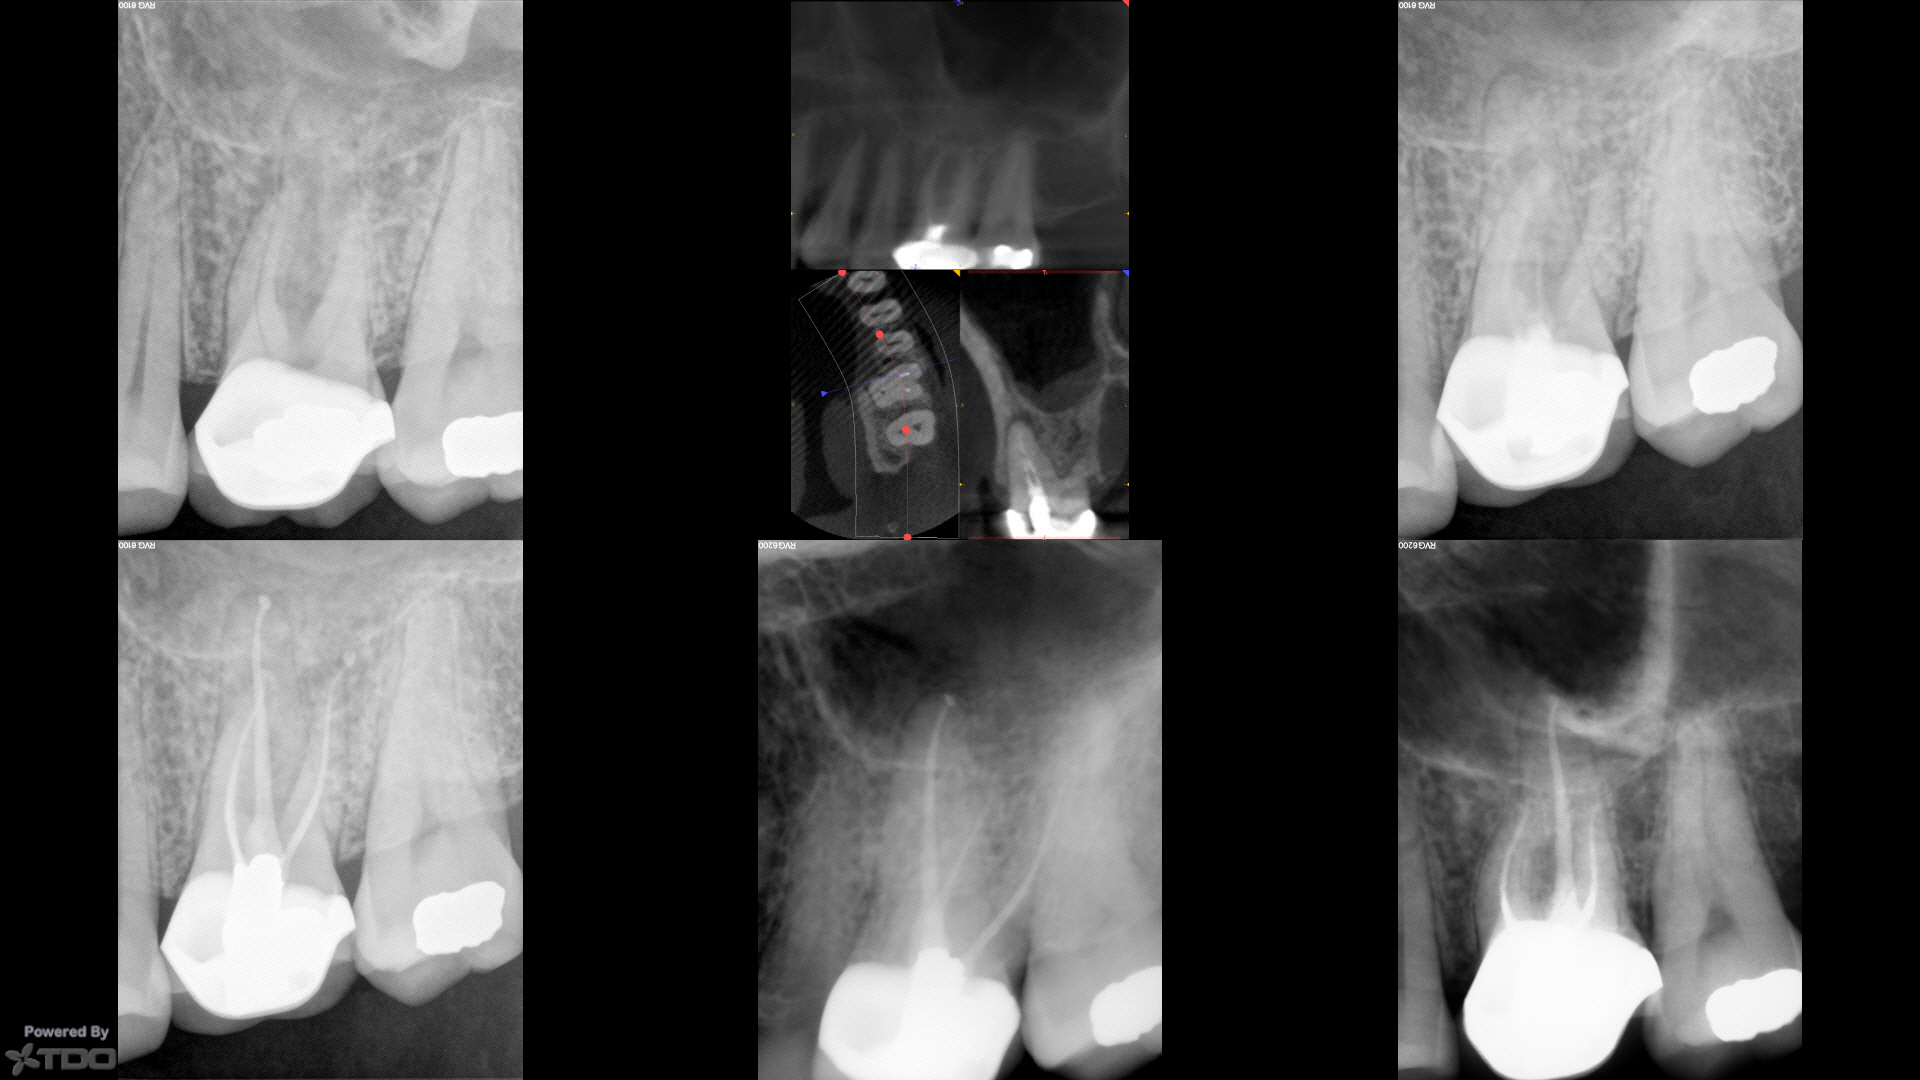

Three year followup on NSRCT with amalgam crown repair

In today for another tooth which I will post under separate cover.

CBCT in CH shows for PONs (points of negotiation).

MB/MB2/DB SS White V-Taper2 17/V.04, P SS White V-Taper2 30/V.06.